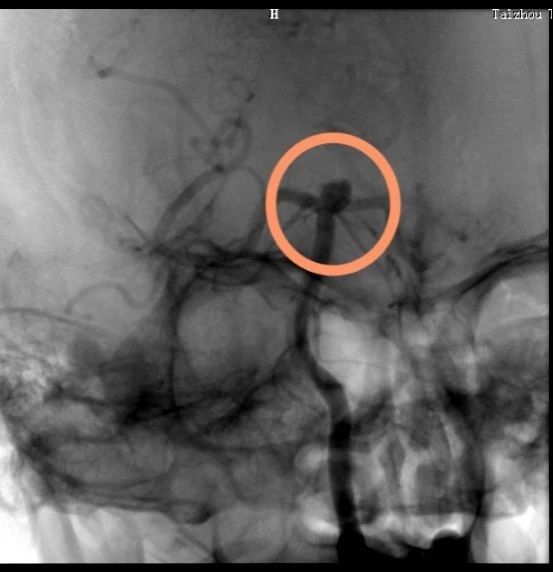

動脈瘤在這里↓↓↓

術(shù)中造影顯示的顱內(nèi)動脈瘤,大家不要小看它,它要是破裂了,可是會要人命的。所以顱內(nèi)動脈瘤又稱為腦子里的定時炸彈。